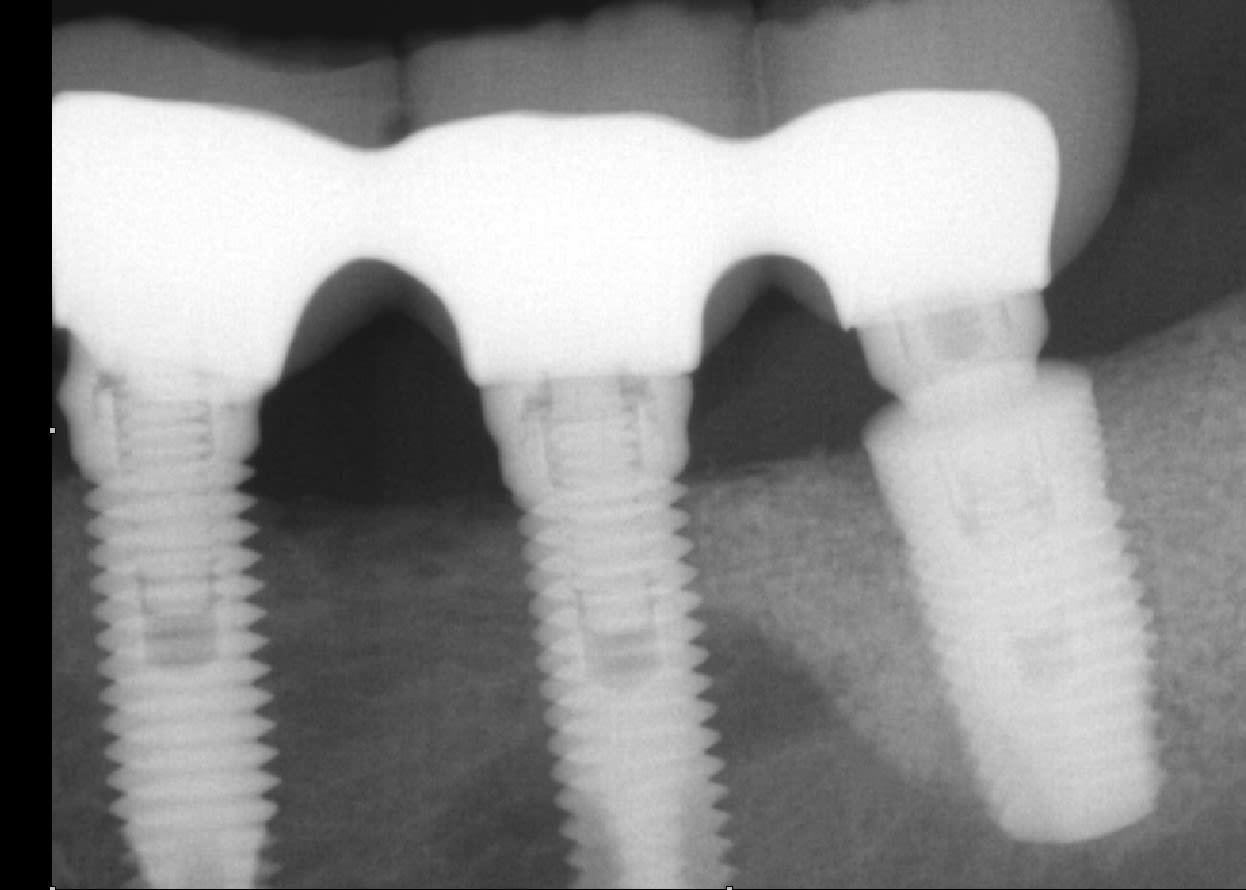

Quelqu'un saurait-il de quelle marque d'implant il s'agit?

Je dois démonter suite à une péri-implantite sur 36.

Les 2 sur la gauche (dommage on voit pas les apex) vraisemblablement des Nobel mk3 hexagone externe

Celui sur la droite c’est un I-Cone Médical Production

Penses tu possible que les 2 de gauche soient aussi des "medical production" HE externe? https://www.medical-production.eu/fr/component/hikashop/product/903-implant-he-externe.html

C’est tout à fait possible….mais ta radio n’étant pas complète sur ces implants, il me manque des détails pour finaliser l’identification

Ce qui va vraiment te dire, c’est la vis, si c’est un genre de torx c’est du Nobel